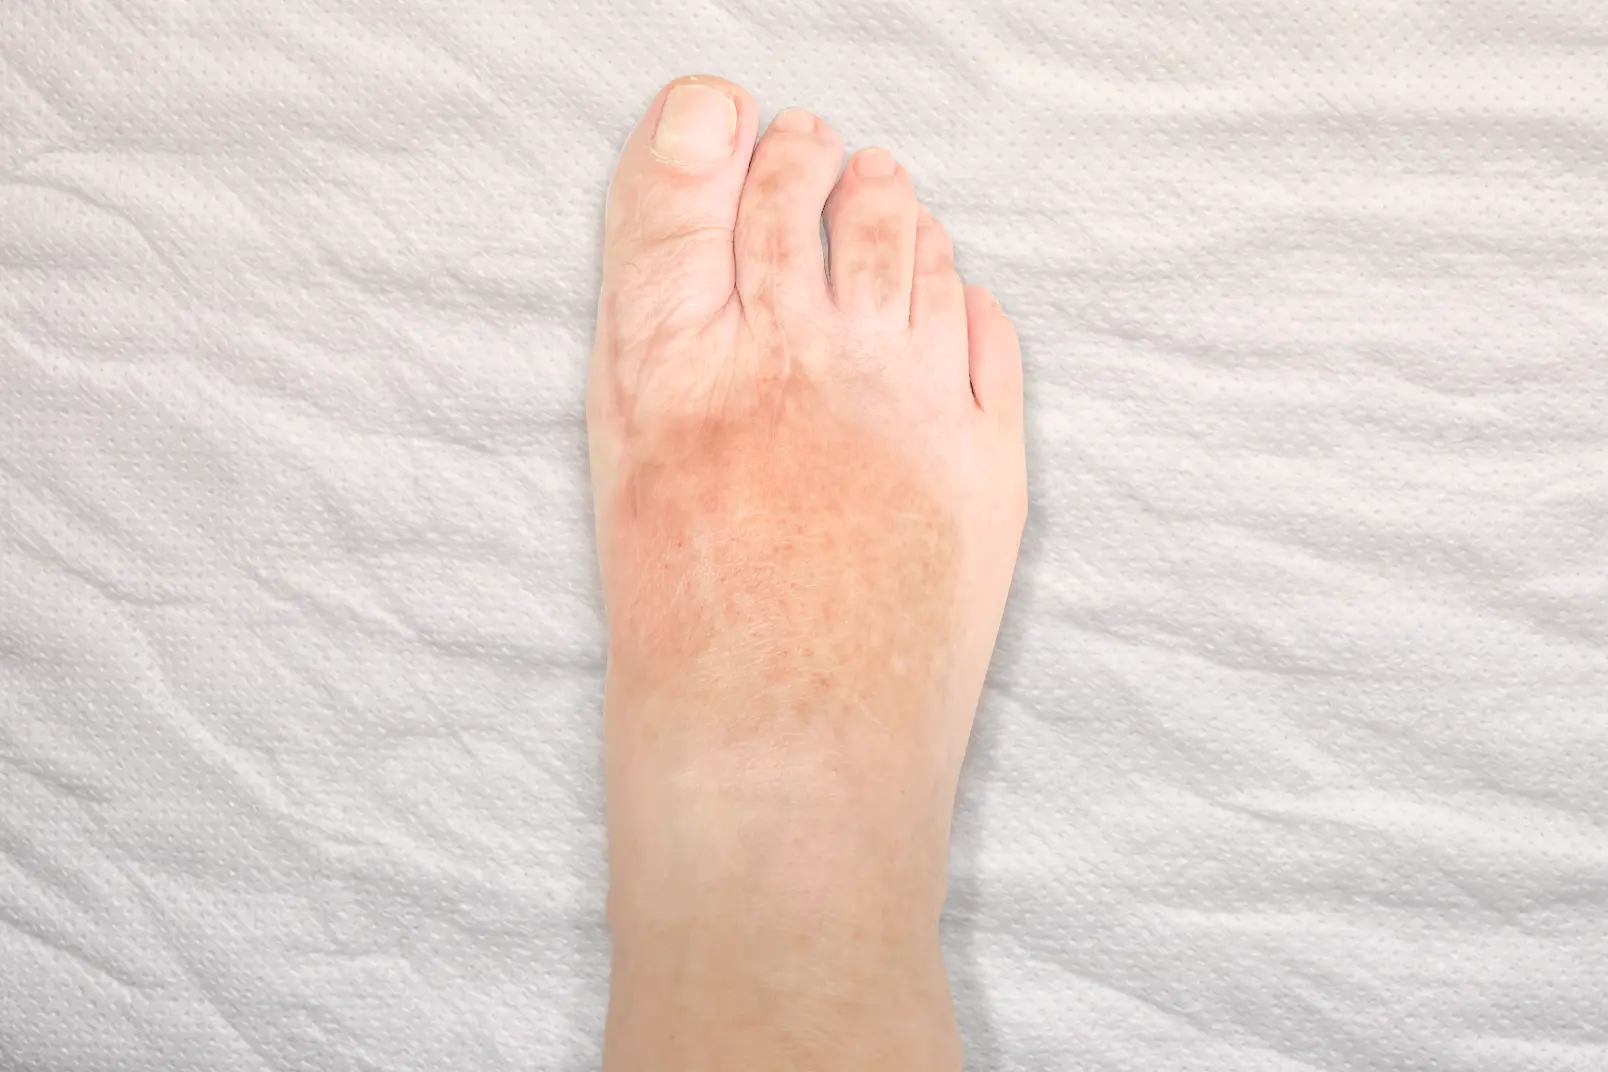

Cirugía de

deformidades

del antepié

El antepié concentra muchas de las patologías quirúrgicas más habituales. Son problemas que suelen avanzar con el tiempo y que, cuando generan dolor o deformidad progresiva, pueden limitar de forma importante la vida diaria. Nuestra especialización quirúrgica, buscando la mínima invasión y la rápida recuperación, incluye, entre otras, la cirugía de:

- Juanetes (hallux valgus).

- Metatarsalgia.

- Neuroma de Morton (radiofrecuencia o cirugía).

- Deformidades de los dedos (dedo en martillo, dedo en garra, dedo en mazo, dedo crossover).

- Reconstrucción del antepié.

- Hallux limitus y hallux rigidus (artrosis del dedo gordo del pie).

En muchos de estos casos el paciente ha probado previamente plantillas, cambios de calzado o tratamientos conservadores. Cuando la deformidad progresa o el dolor persiste, la cirugía del pie permite corregir la causa del problema y mejorar la función.